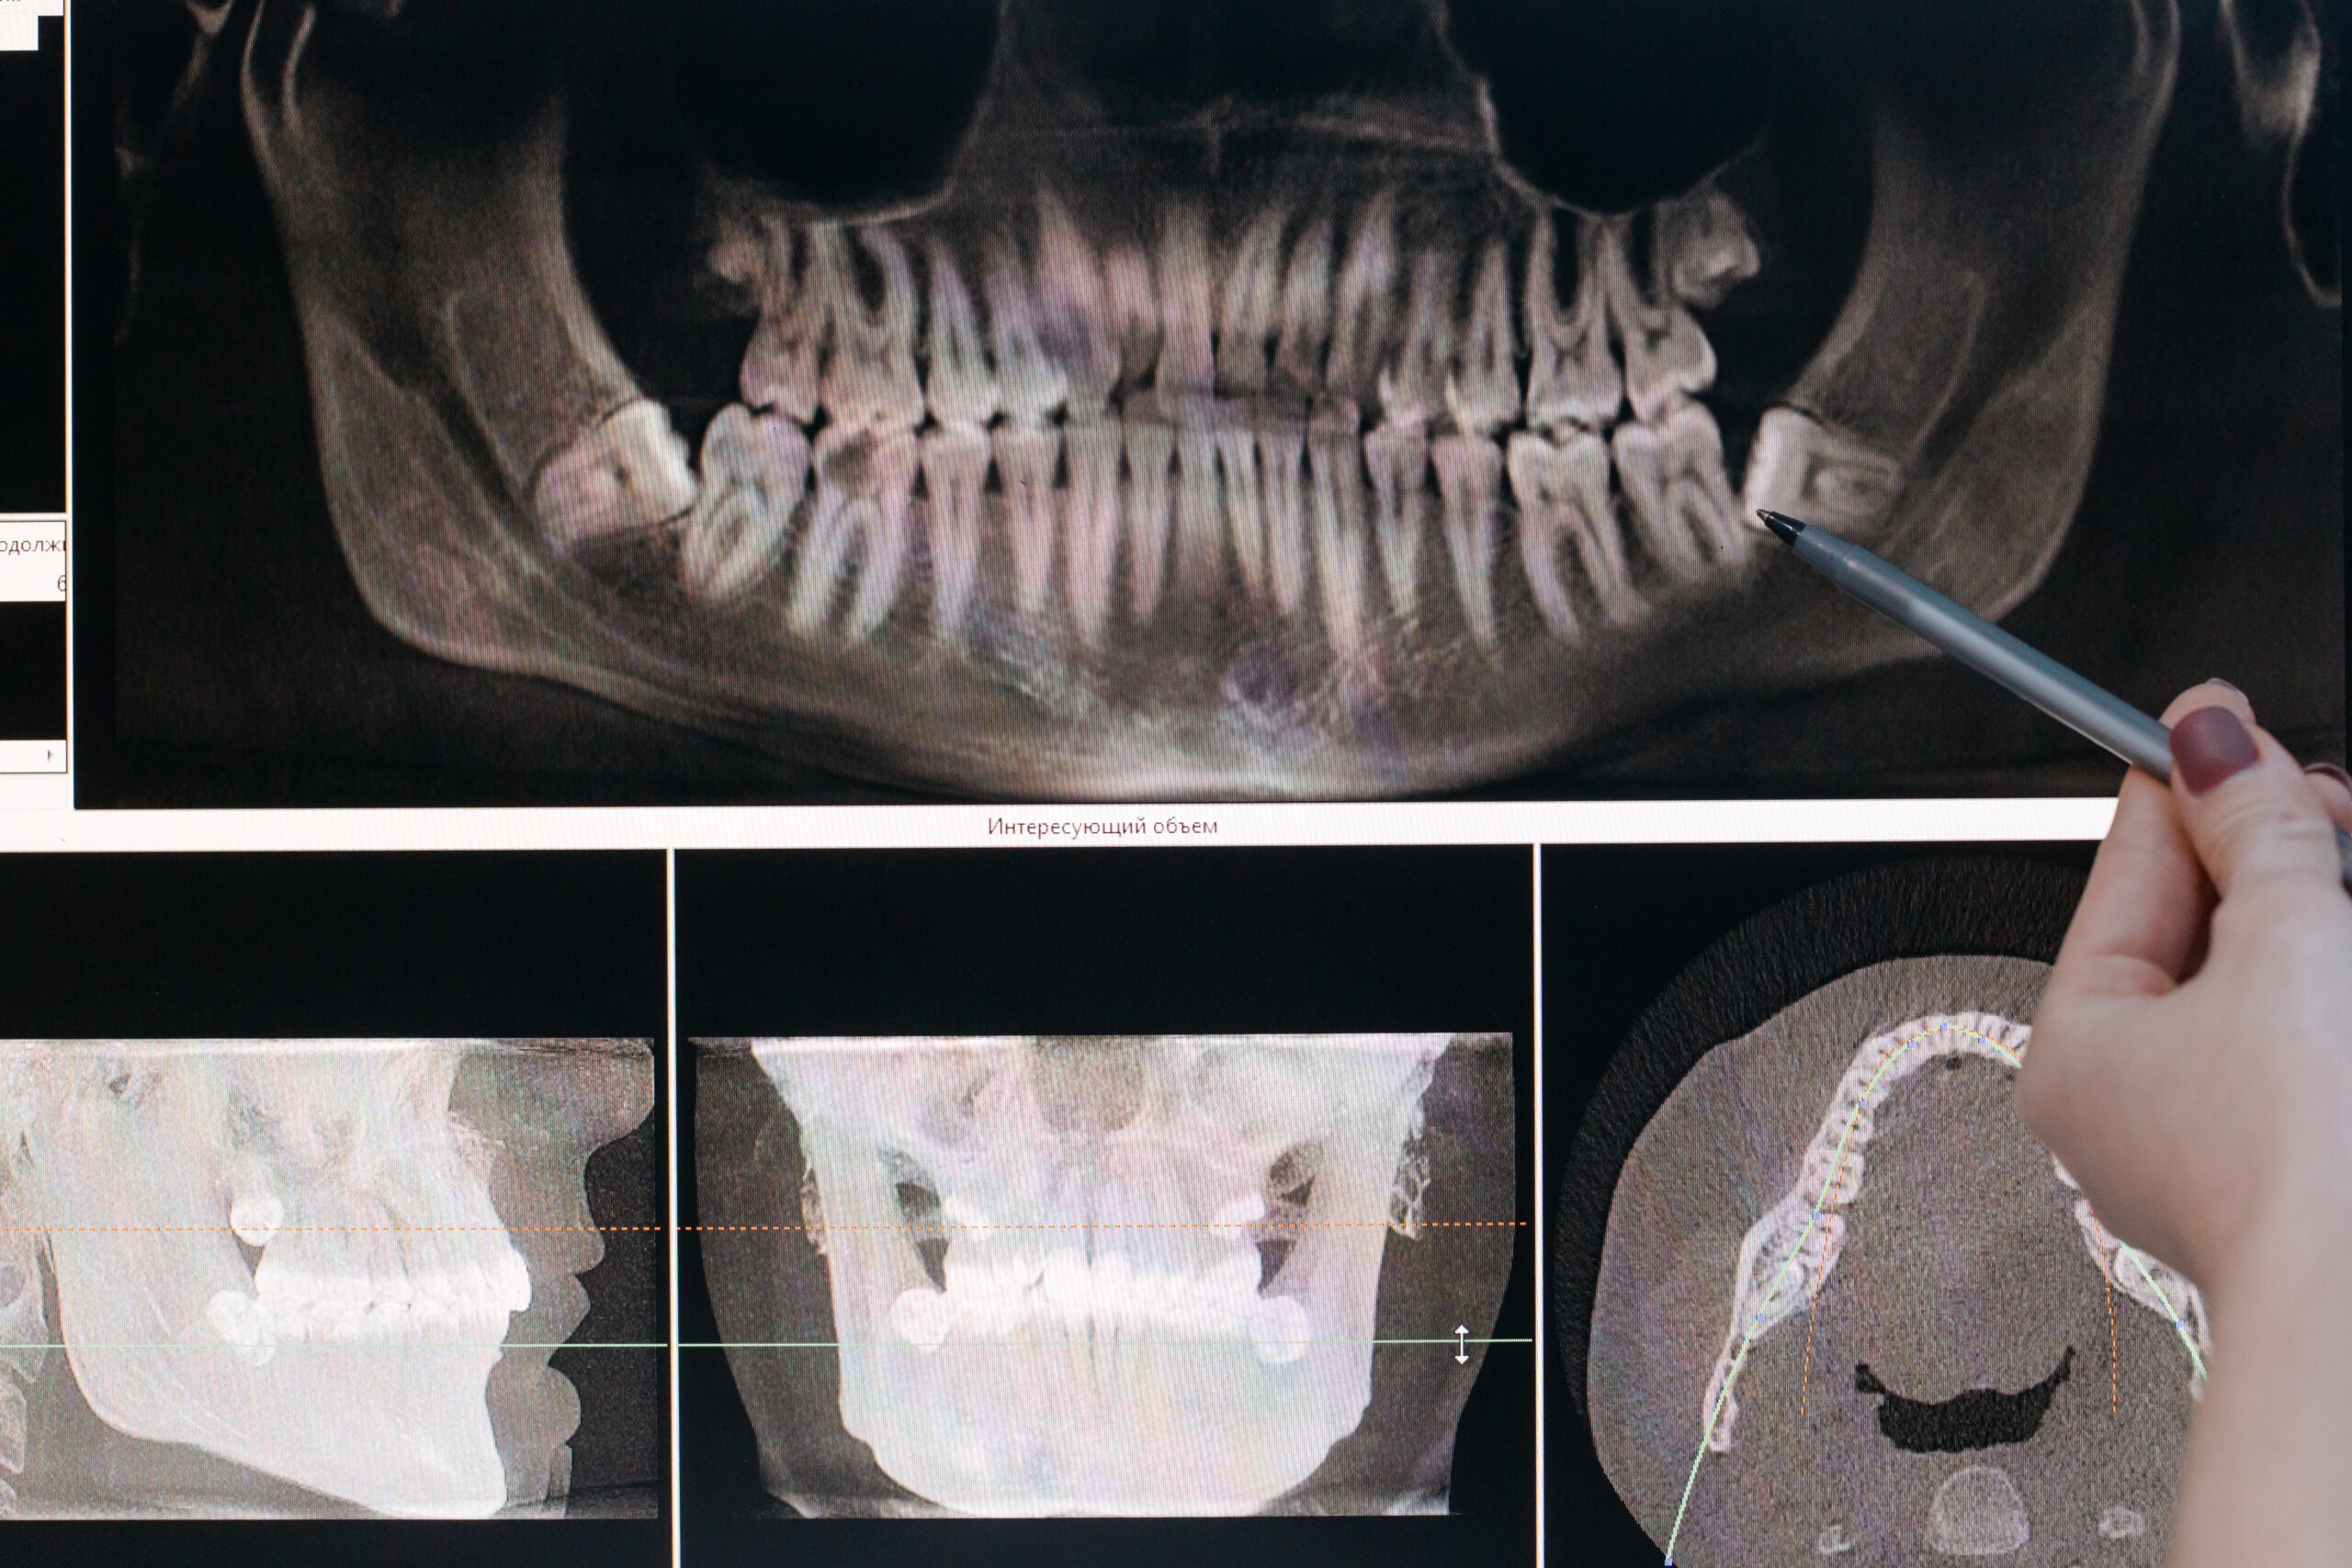

( Açık sinüs lifting, kare split osteotomi, otojen kemik grefleme, kemik içine gömülü 20 yaş diş çekimleri kistler vb…)